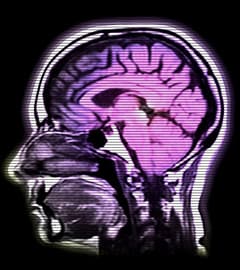

New Book Collects Gay Brain Research Towleroad Gay News